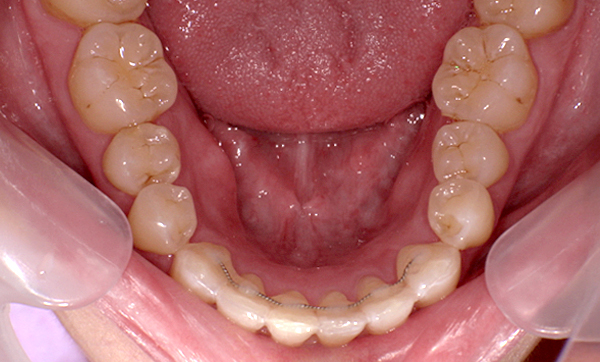

症例_009 「上下の前歯」症例

治療期間:7ヶ月金額:54万円+税20代女性捻転歯一部の反対咬合前歯のガタガタ